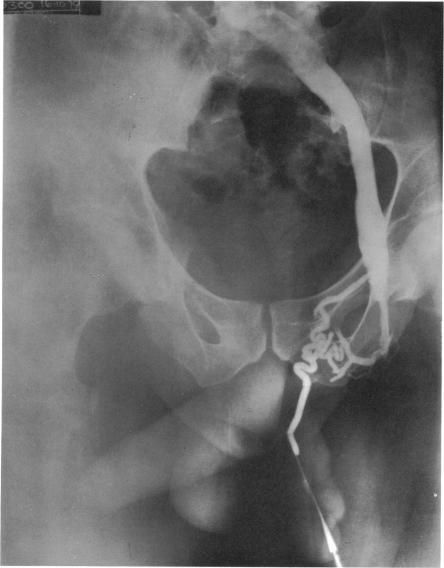

Changes in the appearance of venography after ligation of a varicocele.